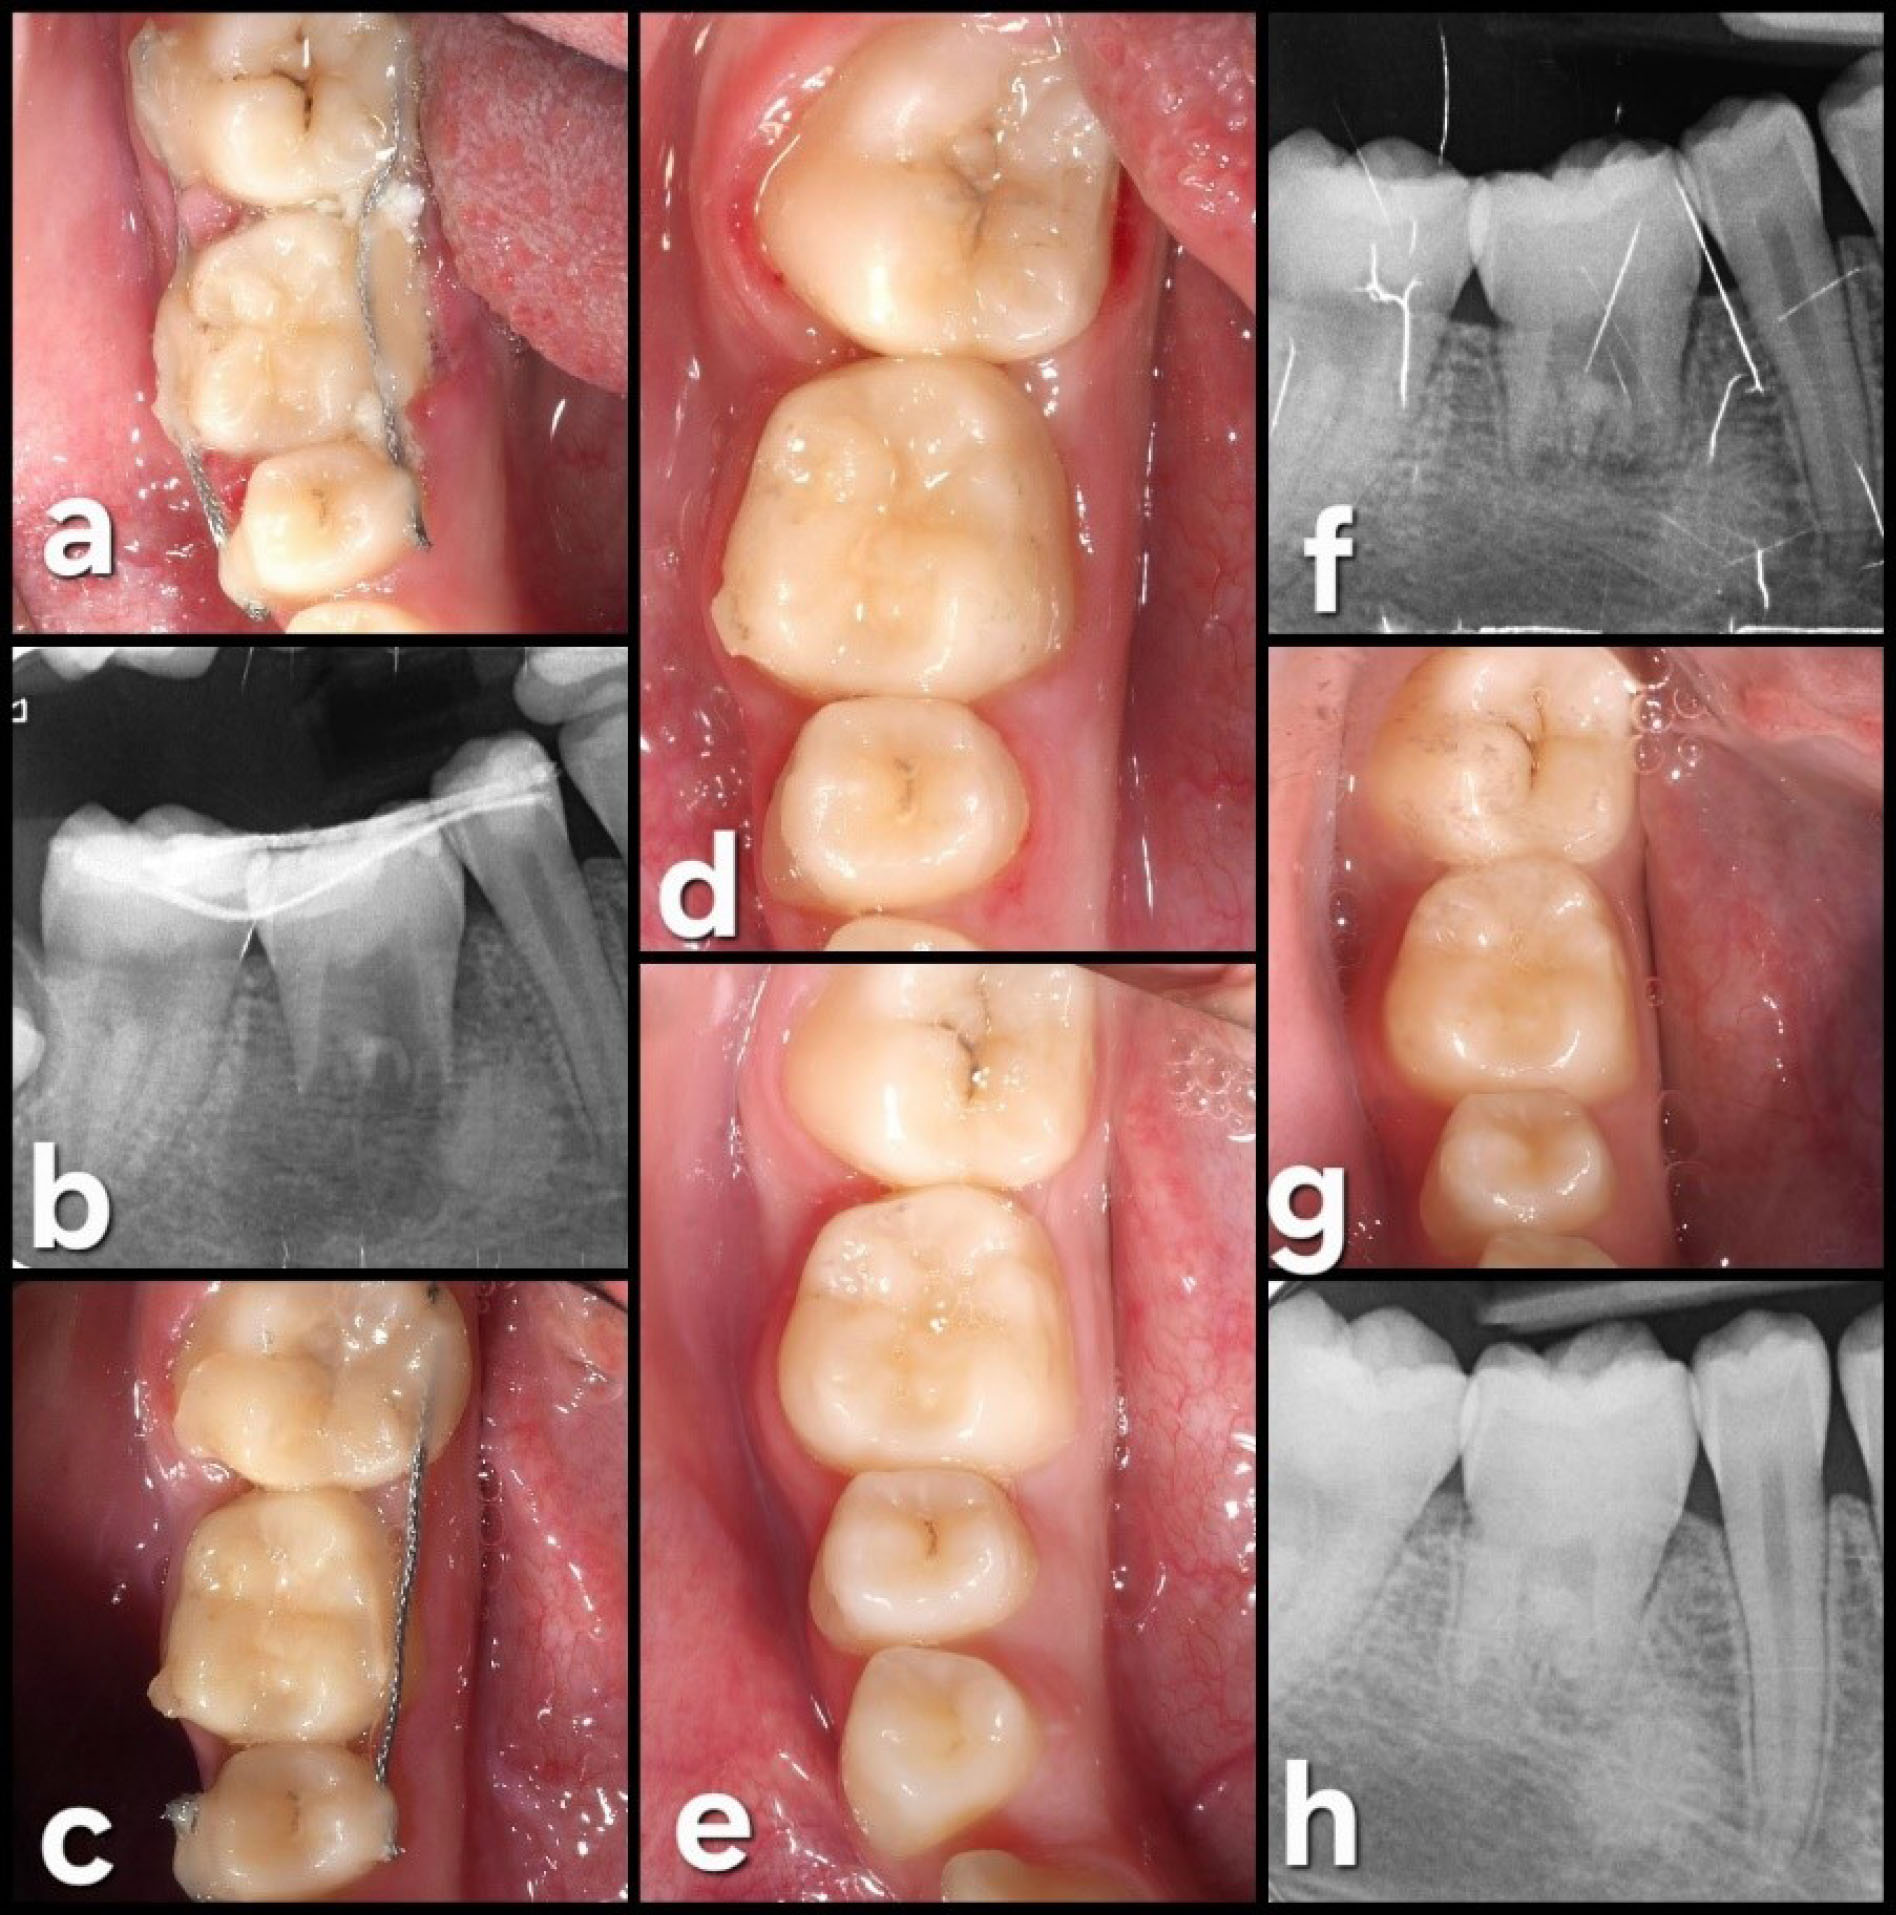

In the last follow-up visit (42 months), the autotransplanted tooth exhibited good health, with a normal periodontal and radiographic exploration. Complete root formation was observed (Figure 7).

Figure 7.

42-month (3.5 years) follow-up. (a) Occlusal view. (b) Lateral view. (c) Periapical radiograph at 42 months showing complete root formation with a complete periodontal ligament (PDL) around the tooth